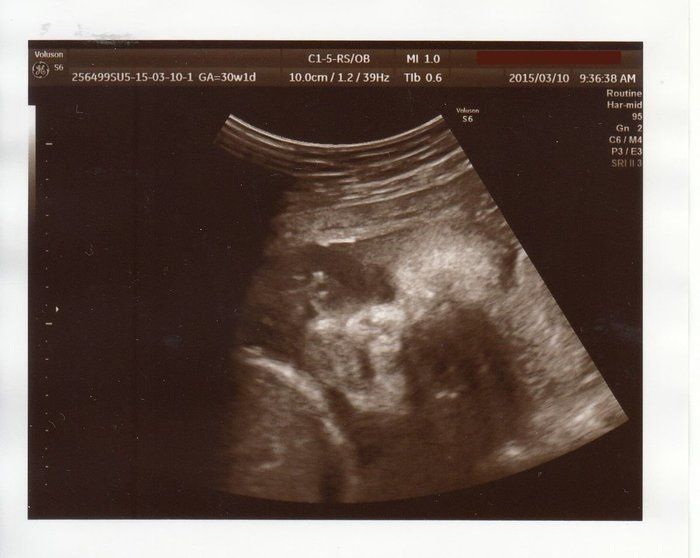

なつさんの妊娠30週目のエコー写真

どんな顔かわかるようになってきました

エコーで顔立ちがはっきり見られるようになりました。チェックしているときにしゃっくりをしていたのも見られました。恒例になっていたおしりチェックをしてもらうと、突然おしりの間に男の子のしるしが! 「今までの検診で何度も見ていたのに、どうして急にわかったんだろう」と家族と驚きました。